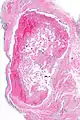

Intravascular papillary endothelial hyperplasia is a rare, benign tumor. It may mimic an angiosarcoma, with lesions that are red or purplish 5-mm to 5-cm papules and deep nodules on the head, neck, or upper extremities.[1][2]: 592

Histopathology Images